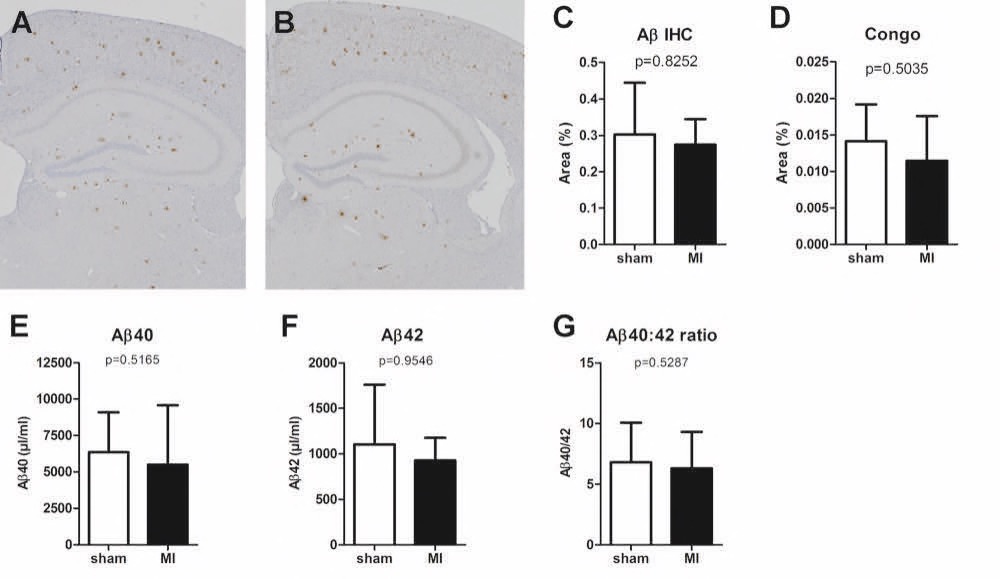

Chapter 6 Figure 7Representative images of the amyloid beta (Aβ) sections in APP/PS1 sham (A) and MI mice (B). No significant differences were detected between sham and MI APP/PS1 mice in Aβ IHC staining (C, n=5, 9), Congo red staining (D, n=4, 9), Aβ40 plasma levels (E, n=6, 9), Aβ42 plasma levels (F, n=6, 9) or the ratio between Aβ40 and Aβ42 plasma levels (G, n=6, 9).